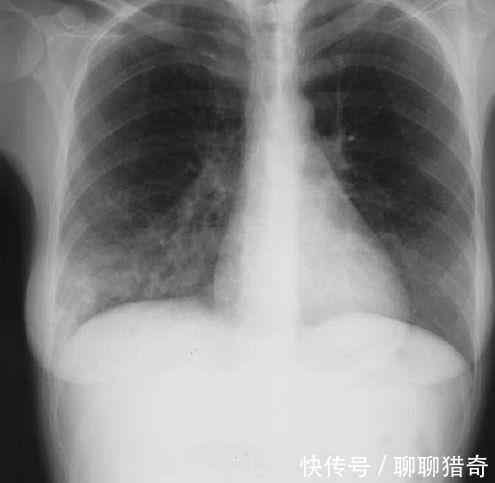

据了解,当时女子一觉醒来后,感觉浑身都特别难受,连忙去医院检查,结果医生给女子拍摄x光片仔细检查,检查后发现女子的身体内有大片阴影。

看完后女子和医生当场都愣住了,因为在女子的体内居然发现大片的铁屑,很难想象这些东西是怎么进入到女子的体内,医生表示也是第一次见到这种情况。